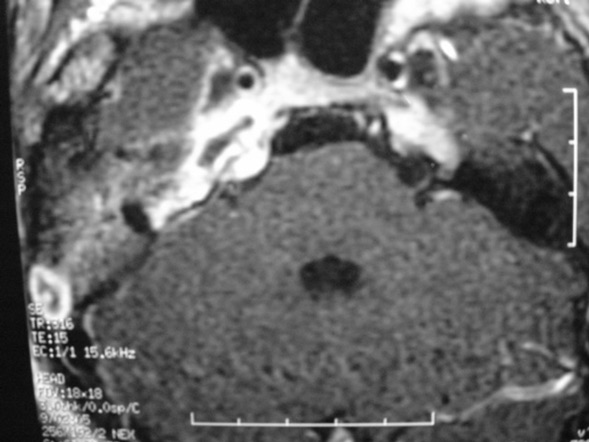

The petrous apex is a relatively inaccessible area that can occasionally harbor serious disease. Disease processes that usually cause symptoms are typically inflammatory or neoplastic in nature. Petrous apex lesions typically cause nonspecific symptoms such as headache, but as the lesion becomes more extensive, adjacent structures such as cranial nerves can become involved. A common early and specific sign of a petrous apex process is abducens palsy. Current imaging techniques can usually provide enough supplemental information to allow a focused plan of treatment. It is important to determine whether a petrous apex lesion can be observed or, if surgical treatment is required, whether a drainage or excision is required. There are various available surgical approaches to the petrous apex. The choice depends on the status of hearing function as well as the suspected pathology, which will dictate whether a drainage or excisional procedure is required.